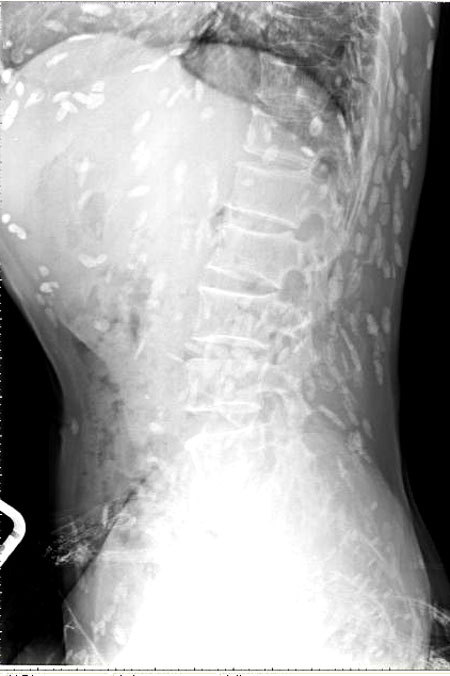

광둥성 푸산시 순더 지역에서 한 남성은 회를 섭취한 뒤, 복부 통증과 피부 가려움증 증상을 겪었습니다. 이로 인해 그는 난팡 의과대학 부속병원을 찾아 진료를 받았습니다. 의사는 이 환자의 증상을 확인하기 위해 엑스레이를 촬영하였고, 이 사진에서는 그의 온몸에 기생충이 퍼져 있는 것을 확인할 수 있었습니다. 이러한 기생충은 촌충 또는 열두 조충이라고 불리는 벌레로서, 사람의 장내에서 기생하는 것으로 알려져 있습니다.